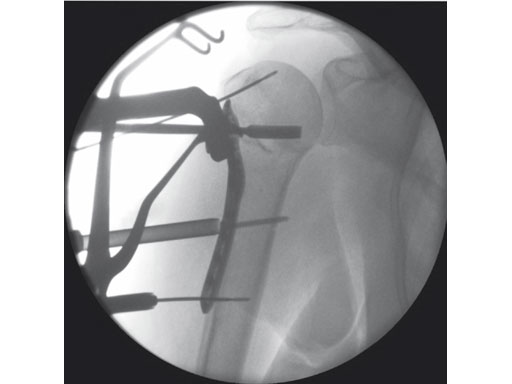

A 76-year-old woman suffered a low-energy fall at home.

Fig 4 Intraoperative view.